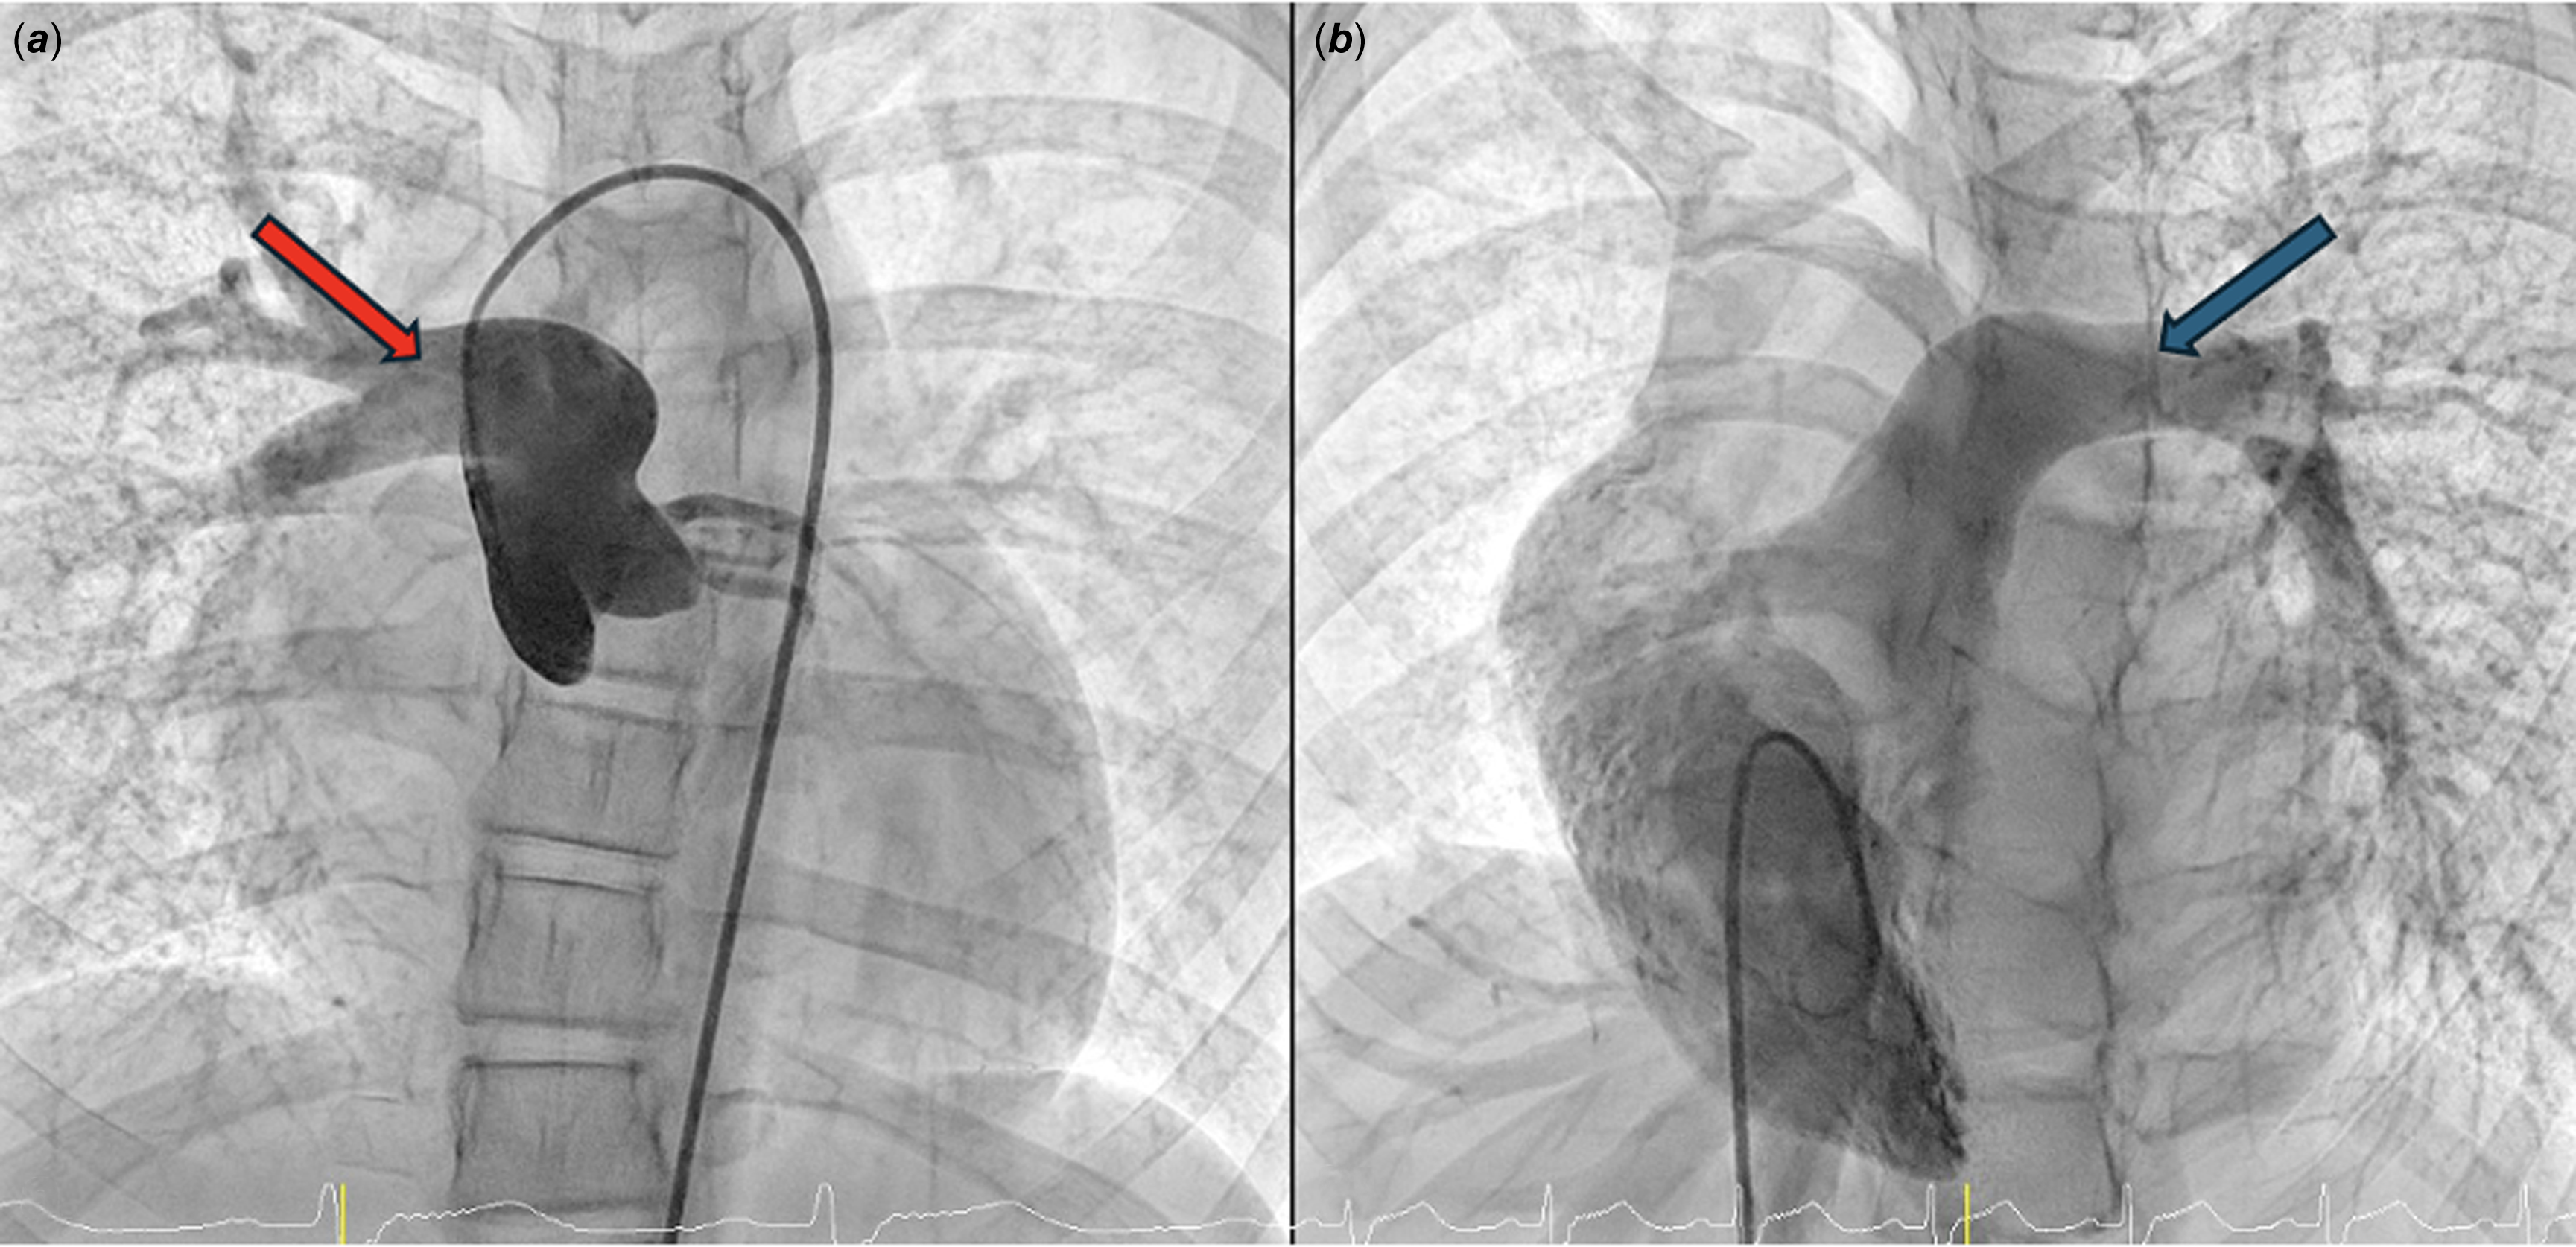

Diagnostic cardiac catheterisation was performed to evaluate the pulmonary circulation further and confirm the diagnosis. Angiography confirmed the anomalous origin of the right pulmonary artery from the ascending aorta (Figure 2a and 2b). Haemodynamic measurements revealed the following pressures (in mmHg): main pulmonary artery: 38/12 (23), left pulmonary artery: 34/13 (25), right pulmonary artery: 98/55 (75), and right ventricle 38/3, pulmonary capillary wedge pressure was 16/15 (14) mmHg, and ascending aorta pressure was measured as 98/57 (73). Shunt and resistance calculations revealed a pulmonary-to-systemic flow ratio (Qp/Qs) of 0.75 and a pulmonary vascular resistance-to-systemic vascular resistance ratio of 1.25.

Figure 2. ( a ) Angiographic image demonstrating the anomalous origin of the right pulmonary artery from the ascending aorta, following a posterior and medial course(red arrow). ( b ) Right ventricular injection illustrating the continuity between the main pulmonary artery and the left pulmonary artery (blue arrow).